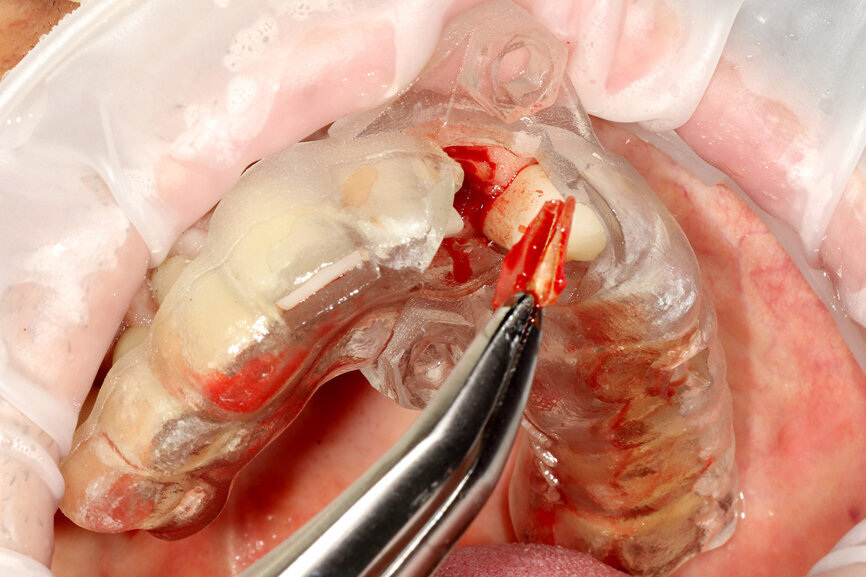

Fig. 12a: A post fracture presenting in the left central incisor, requiring extraction.

Fig. 12b: The occlusal view illustrated the cervical tissue volume and contours.

A 62-year-old male patient presented with a hopeless prognosis for a post fracture in the left central incisor requiring extraction (Figs. 12a & b). The preoperative periapical radiograph revealed an existing implant supporting a metal–ceramic restoration for the adjacent region #11 (Fig. 13). The CBCT (CS 9600, Carestream Dental) cross-sectional image revealed a favourable preoperative condition relating to the trajectory of the endodontically treated root to the alveolus for a PET procedure (Fig. 14a). Using the native Carestream 3D Imaging software, a simulated implant and abutment projection was positioned within the available bone to avoid the root fragment (Fig. 14b).